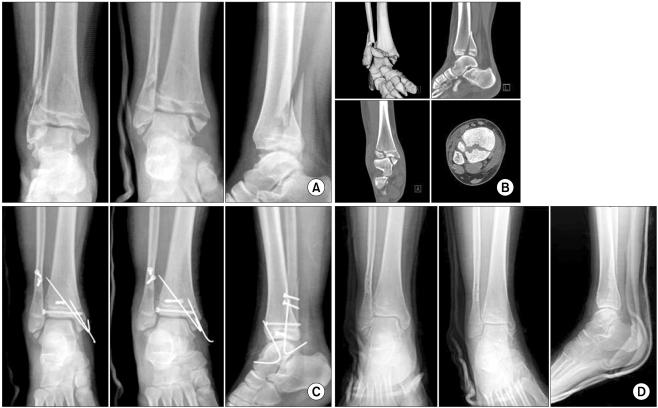

Among the 14 cases, 11 were triplane fractures and 3 were Tillaux fractures. Seven were two part triplane fractures, and 4 were three part triplane fractures. Eight were lateral triplane fractures, and 3 were medial triplane fractures. A fibula fracture was accompanied by 7. The fibular fracture comprised of oblique fractures in all cases. A closed and open reduction was performed in 6 and 8 cases, respectively. All but one showed excellent treatment outcomes at the final follow-up. Traumatic arthritis developed in 1 case.

Precisely detecting the fracture configuration by computed tomography and understanding the injury mechanism have greatly improved the outcomes of triplane fractures and Tillaux fractures of the ankle in adolescent patients.